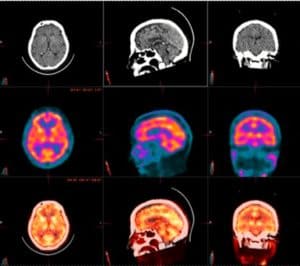

Perfuzie miocardică

Detectorii digitali care captează un număr maxim de fotoni oferă imagini 3D detaliate, superioare tehnologiei planare Anger. Sistemul SPECT/CT multifuncțional permite scanări complete cap–picioare într-o singură sesiune, oferind informații precise și reducând disconfortul pacientului.

- Îmbunătățirea detecției leziunilor este doar începutul. O singură scanare completă oferă imagini 3D de tip PET, reducând timpul de examinare și permițând utilizarea unei doze mai mici, optimizând modul de desfășurare al investigațiilor imagistice.

- Algoritmi de procesare de ultimă generație Sistemele VERITON și VERITON-CT sunt echipate cu algoritmi sofisticați de procesare a imaginilor, pentru o calitate la cel mai înalt nivel. Printre opțiuni se regăsesc reconstrucția iterativă OSEM cu recuperare a rezoluției, corecția atenuării (AC), corecția dispersiei (SC), corecția volumului parțial (PVC), corecția energiei înalte (HEC) și altele.